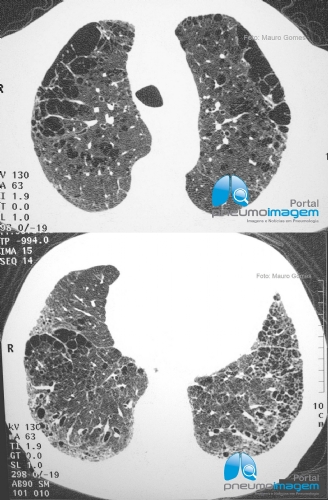

CASO CLÍNICO #54Homem de 72 anos de idade com queixa de dispneia intensa, mas com espirometria normal. Qual o diagnóstico? Deixe seus comentários abaixo.

Man 72 years of age with severe dyspnea, but with normal spirometry. What is the diagnosis? Write your comment below.

Associação de enfisema e fibrose pulmonar. Espirometria normal porque tem componentes obstrutivo (Enfisema) + restritivo (fibrose) Diminuiçaõ da DLCO e Hipertensão Pulmonar são frequentes.

Associação de Fibrose pulmonar e Enfisema

Fibroenfisema - investigar HP, complicação frequente.

Fibrose pulmonar tabaco relacionada. Dpoc com fibrose. Espirometria é normal porque tem os dois componentes fibrose e enfisema